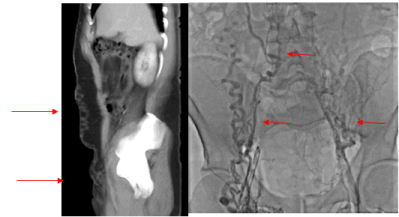

He presented with worsening bilateral lower extremity pain, edema, bilateral phlegmasia cerulea dolens and varicoceles. Estimated Clinical-Etiology-Anatomy-Pathophysiology (CEAP) classification at presentation was C4a. Lower extremity Doppler showed chronic non-occlusive right iliofemoropopliteal DVT and chronic non-occlusive left femoropopliteal DVT. CT abdomen and pelvis with intravenous contrast demonstrated extensive chronic thrombosis of the IVC below the IVC filter as well as bilateral common/external iliac veins with blood from bilateral common femoral veins draining through anterior abdominal wall collaterals into the anterior thoracic vein and recanalized umbilical vein (Figures 1 and 2).

Figure 2a and 2b. CT with venous phase and initial bilateral venogram showing extensive pelvic and abdominal collaterals and complete IVC and bilateral iliac vein occlusion.